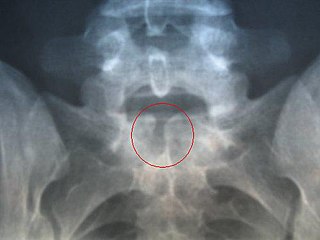

Occulta is Latin for "hidden". This is the mildest form of spina bifida.[17] In occulta, the outer part of some of the vertebrae is not completely closed.[18] The splits in the vertebrae are so small that the spinal cord does not protrude. The skin at the site of the lesion may be normal, or it may have some hair growing from it; there may be a dimple in the skin, or a birthmark.[19] Unlike most other types of neural tube defects, spina bifida occulta is not associated with increased AFP, a common screening tool used to detect neural tube defects in utero. This is because, unlike most of the other neural tube defects, the dural lining is maintained.

Many people with this type of spina bifida do not even know they have it, as the condition is asymptomatic in most cases.[19] About 15% of people have spina bifida occulta,[8] and most people are diagnosed incidentally from spinal X-rays. A systematic review of radiographic research studies found no relationship between spina bifida occulta and back pain.[20] More recent studies not included in the review support the negative findings.[21][22][23]